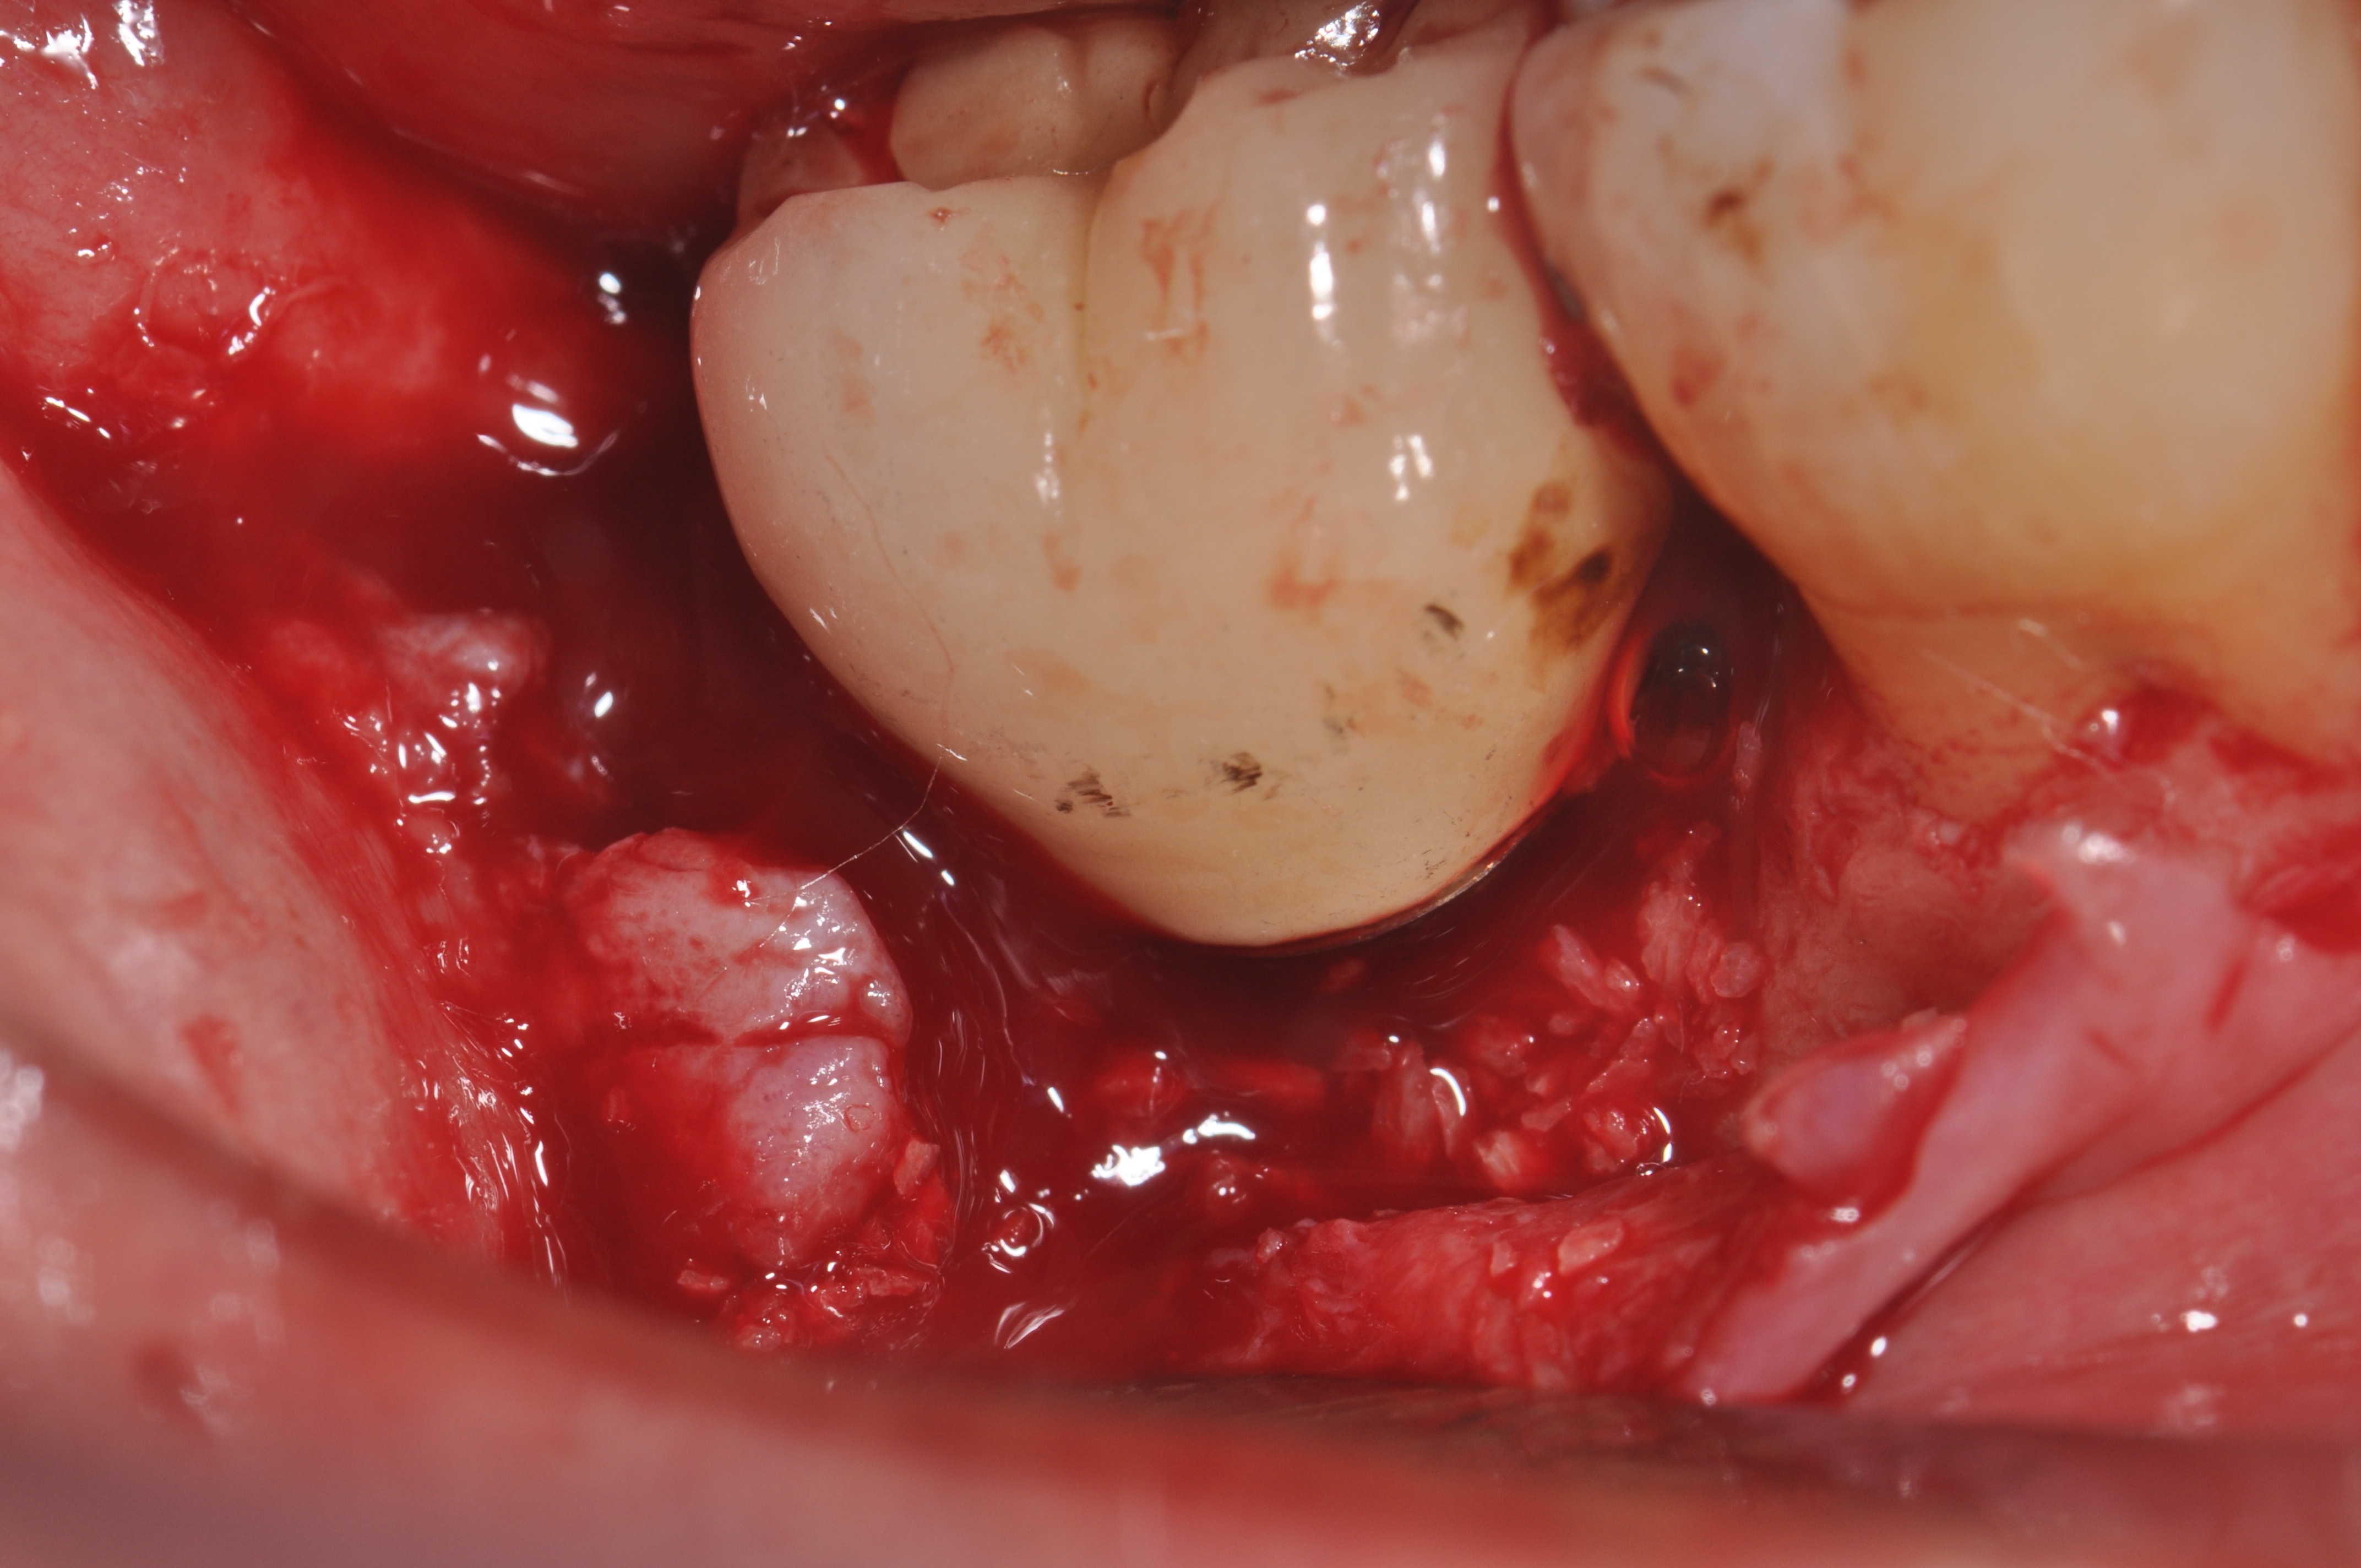

Clinical exposure of a circumferential lesion that demonstrates 3 mm of bone loss. No cement was present, suggesting that the lesion was of bacterial origin. Surface decontamination included citric acid.

Figure 2